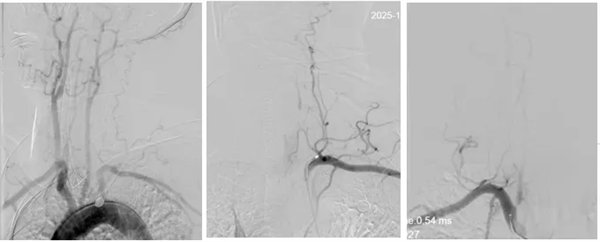

為最大程度搶救腦細胞,縮短腦組織供血恢復間隔,神經內三科卒中救治團隊立即啟動綠色通道實施介入取栓治療,麻醉醫師迅速抵達導管室,神經內三科主任席聰對患者進行急診血管造影后發現:患者左椎動脈起始段閉塞,右椎動脈起始部次全閉塞。

術中,介入團隊精準定位血管閉塞部位,通過微導絲“探路”聯合球囊擴張技術開通右側椎動脈開口,造影椎開口殘余狹窄60%?;讋用}血栓形成,基底動脈管腔狹窄55%,基底動脈尖堵塞,右側大腦后動脈及小腦上動脈未見顯影,左側大腦后動脈P3以遠閉塞。

席聰準確鎖定患者基底動脈處血栓,采用抽吸取栓技術快速開通血管,成功取出堵塞部位2cm的血栓。再次造影示:右側大腦后及雙側小腦上動脈再通,右側大腦后動脈P3段以遠閉塞,考慮慢性閉塞,推注替羅非班,血流明顯加快。隨后采用支架植入術開通右側椎動脈開口處,術中影像顯示:支架貼壁良好,無明顯殘余狹窄,顱內血管顯影良好。